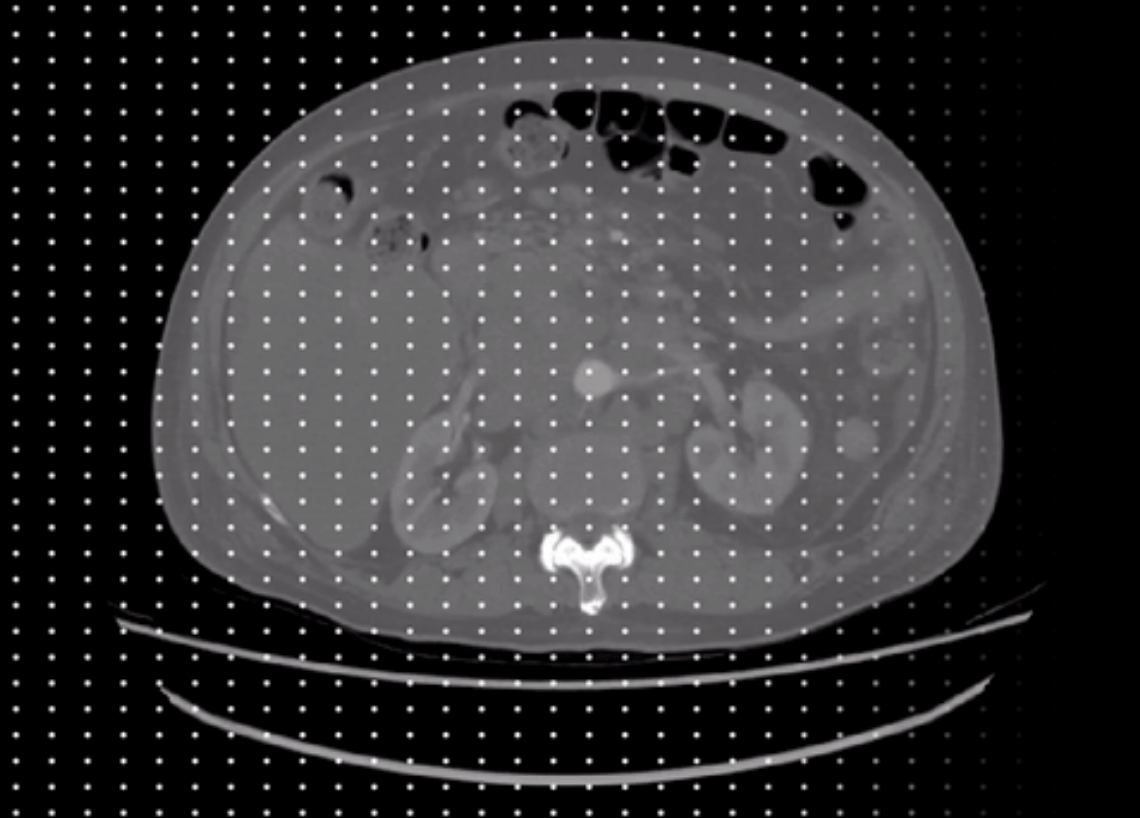

我们的测试策略包括Everything模式:自动分割 (S1H, S1B)以及Prompt模式:单个正样本点 (S2)、五个正样本点 (S3)、五个正样本点和五个负样本点 (S4)、单个方框 (S5)、单个方框和单个正样本点(S6),图3展示了我们设计的SAM测试框架。

图3 本研究设计的SAM详细测试框架。

- Everything模式不适用于大多数医学影像分割任务。在这种模式下,SAM对医学分割目标的感知能力较差,会输出大量的假阳性预测掩膜(图5)。

- 在Everything模式下,作为提示的网格采样点数量会在一定程度上影响分割性能,如图6所示。这是一个分割性能和测试效率的权衡。

图5 Everything模式的可视化结果。

图6 Everything模式下网格采样点数量对分割性能的影响